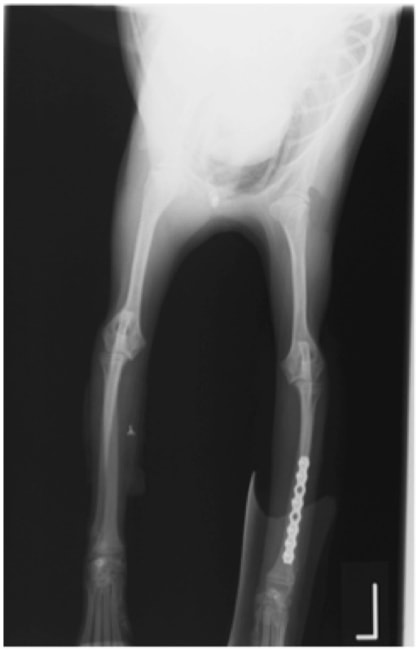

トイプードル 右遠位橈尺骨短斜骨折のALPSによる内固定